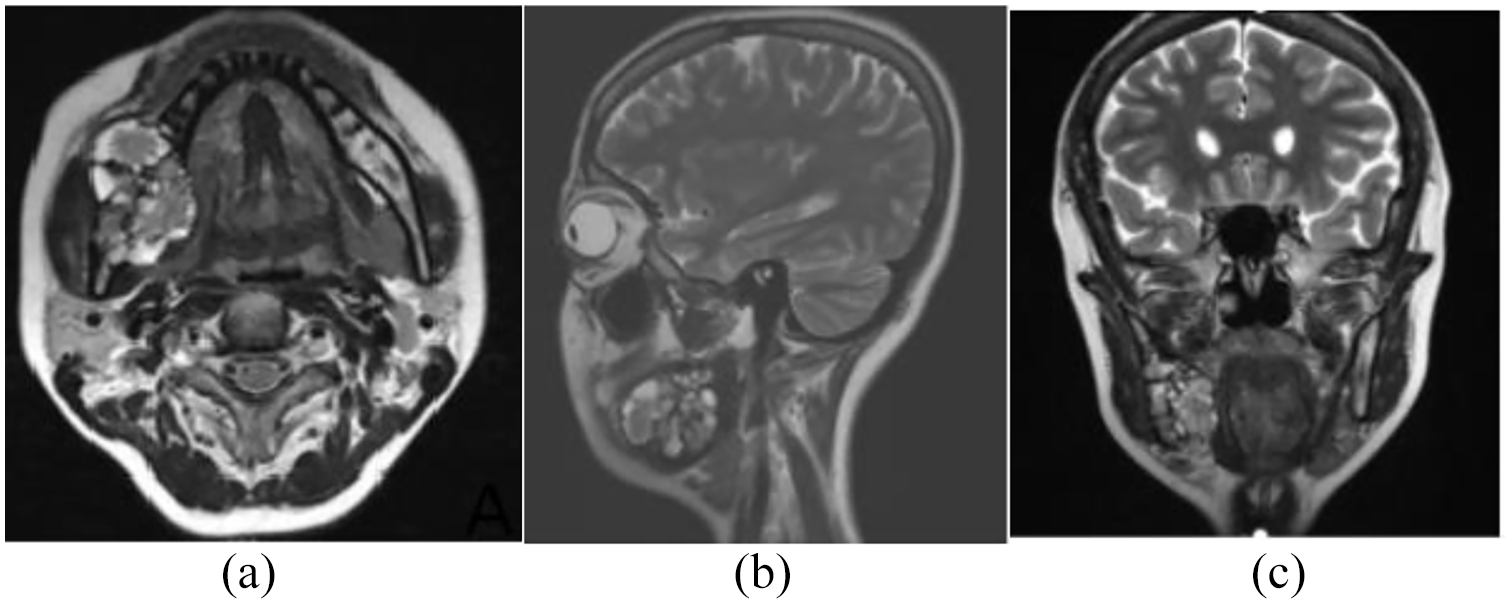

A 25-year-old female with recurrence of an ameloblastoma was referred to the Wuwei Heavy Ion Center (WWHIC) for carbon ion therapy. She had been initially diagnosed with ameloblastoma 8 years ago and underwent curettage of rigmandible ameloblastoma; postoperation pathology showed multicystic ameloblastoma, clear margin in 2012. In 2020, the patient had pain of right mandible; a mass was found on a magnetic resonance imaging (MRI) scan (Figure 1) in the same sitting at the right mandible, and the mass size is 4.7 cm×3.6 cm×2.7 cm—2months later, she came to our center with complaining of increasing pain and swelling in the right mandible. She was administered a small partly enucleation biopsy of the tumor, confirming the diagnosis of locally recurrent multicystic ameloblastoma. Maxillofacial surgeon recommended surgery to remove the tumor, faced with the inherent morbidity, artificial metal material implant and complex reconstruction, as well as facial aesthetics and cosmetic requirements, but the patient refused to undergo operation and wanted to treat with carbon ion radiotherapy. After multidisciplinary discussion, she received a dose of 60Gy (relative biological effectiveness (RBE)) carbon ions. The patient was immobilized in a supine position with a head and neck. A 3-mm-thick computed tomography (CT) image is obtained using a CT simulator. Target volume and organ-at-risk delineation was performed using CT-MRI image fusion. Gross tumor volume (GTV) consisted of macroscopic disease. Planning target volume (PTV) was defined as GTV plus a 5-mm margin. CIRT was performed with an anterior–posterior and a right lateral portal. The prescribed total dose was 60.0 Gy (RBE) in 12 fractions (Fx) with a fraction size of 6 GyE, administered five times per week, from Monday to Friday. Doses of carbon ions were expressed in photon equivalent doses (GyE), which were defined as the physical doses multiplied by the RBE of the carbon ions; the RBE of the carbon ions was assumed to be 3.0. [4,5]

Figure 1. Extensive ameloblastic carcinoma originating from the right mandible, T2 weighted MRI: (a) axial view, (b) sagittal view, and (c) coronal view.